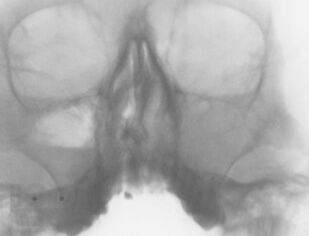

Хронический риносинусит

Представлены данные об этиологии, патогенезе, классификации форм хронического синусита. Приведен обзор современных методов диагностики и лечения. Обсуждается консервативное лечение синуситов с учетом особенностей микрофлоры, освещены не только стандартные хирургические подходы, но и некоторые базовые и прикладные вопросы функциональной эндоскопической риносинусохирургии.